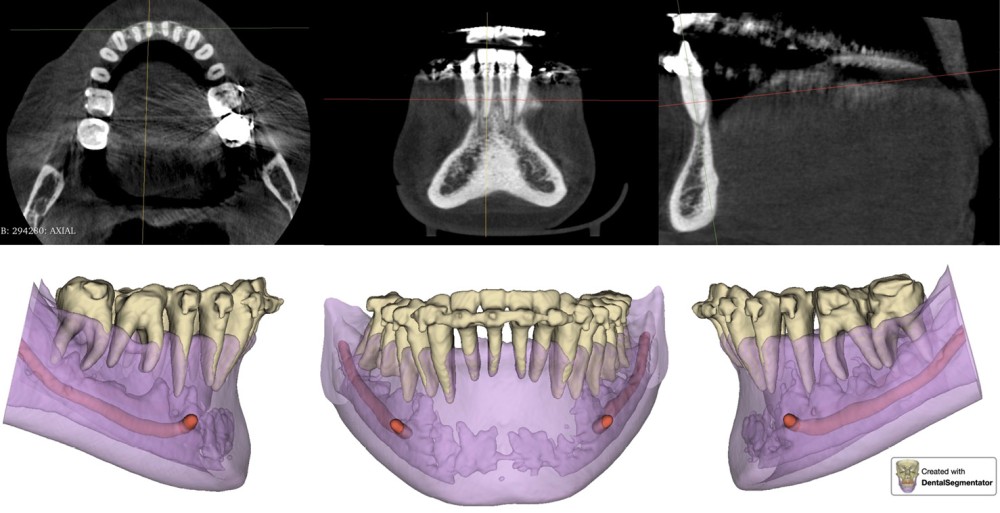

En raison de l’ancrage dentaire postérieur mandibulaire très limité, il est décidé d’utiliser des ancrages osseux pour l’ingression du bloc incisivo-canin mandibulaire, afin de niveler l’arcade et de recréer le surplomb nécessaire à la fermeture des diastèmes maxillaires. Deux minivis d’ancrage sont positionnées entre les dents 32/33 et 42/43, après réalisation d’un examen CBCT localisé sur l’arcade mandibulaire (fig. 7 et 8). Ces minivis antérieures ont été rapidement déposées, en raison de leur mobilité et de la gêne importante de la patiente liée au positionnement très apical du fait de l’alvéolyse.

Des minivis d’ancrage sont alors positionnées entre les dents 34/35 et 44/45 (fig. 9). Un sectionnel d’ingression antérieur (acier .018x.025) est fixé sur celles-ci, tout en passant par des tubes en croix situés entre les prémolaires afin d’éviter le dévissage des minivis. L’ingression est réalisée via des ligatures reliant l’arc orthodontique principal (TMA .018x.025 avec boucles double-delta) au sectionnel, selon une direction permettant l’ingression tout en limitant la composante de vestibulo-version. Du stripping mandibulaire a été réalisé de mésial de 33 à mésial de 43 afin de corriger l’indice de Bolton.